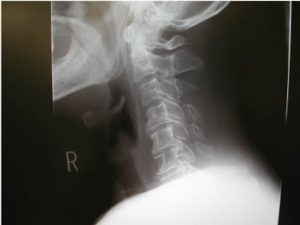

頸椎椎間板ヘルニアとは、首の骨である頸椎の間に存在する椎間板が損傷し、中の髄核が飛び出して神経を圧迫する疾患です。

この状態になると、首や肩甲骨周辺に痛みが生じるほか、手足のしびれや筋力低下といった症状が現れることがあります。頸椎は7つの骨で構成されており、それぞれの間にある椎間板は衝撃を吸収するクッションの役割を果たしています。

しかし、加齢による組織の変性、不良姿勢、交通事故やスポーツによる外傷などが原因で椎間板の外側に亀裂が入り、髄核が飛び出すことで発症します。

診断にはレントゲンやMRI・CT検査が用いられ、神経圧迫の有無を確認します。治療法としては保存療法(薬物療法やリハビリテーション)や手術療法がありますが、手術は最終手段として検討されます。